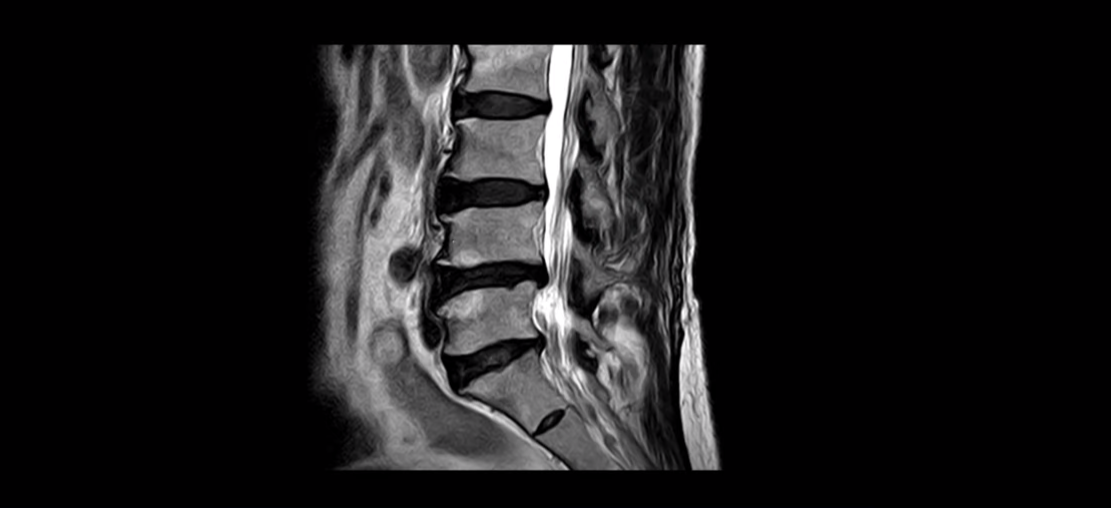

협착증은 노화 때문에 생기는 질환입니다. 나이가 들수록 노화와 퇴행 때문에 신경 구멍이 조금씩 좁아집니다. 이분도 신경 구멍이 좁아져 있습니다. 보시다시피 척추 여러 마디가 퇴행되어 있고

척추관도 좁아져 있고

오른쪽 신경이 빠져나가는 추간공도 두 마디가 좁아져 있지만

좁아진 게 많이 심해 보이지는 않습니다. 그런데 이분이 갑자기 아프게 된 건 불과 2-3달 전입니다. 그럼 1년 전에 전혀 안 아팠을 때 MRI를 찍었다면 최근에 아플 때 찍은 MRI와 많이 달라 보일까요? 정답은 거의 차이가 없다입니다. 아프기 전이나 아픈 후나 MRI로 보이는 신경 구멍의 크기가 같다면 그럼 왜 갑자기 2-3달 전에 극심하게 아픈 증상이 생겼을까요? 그건 약해진 허리 주변 근육에 문제가 생겼기 때문입니다. 어떤 근육 문제가 이런 다리 방사통을 만들까요?